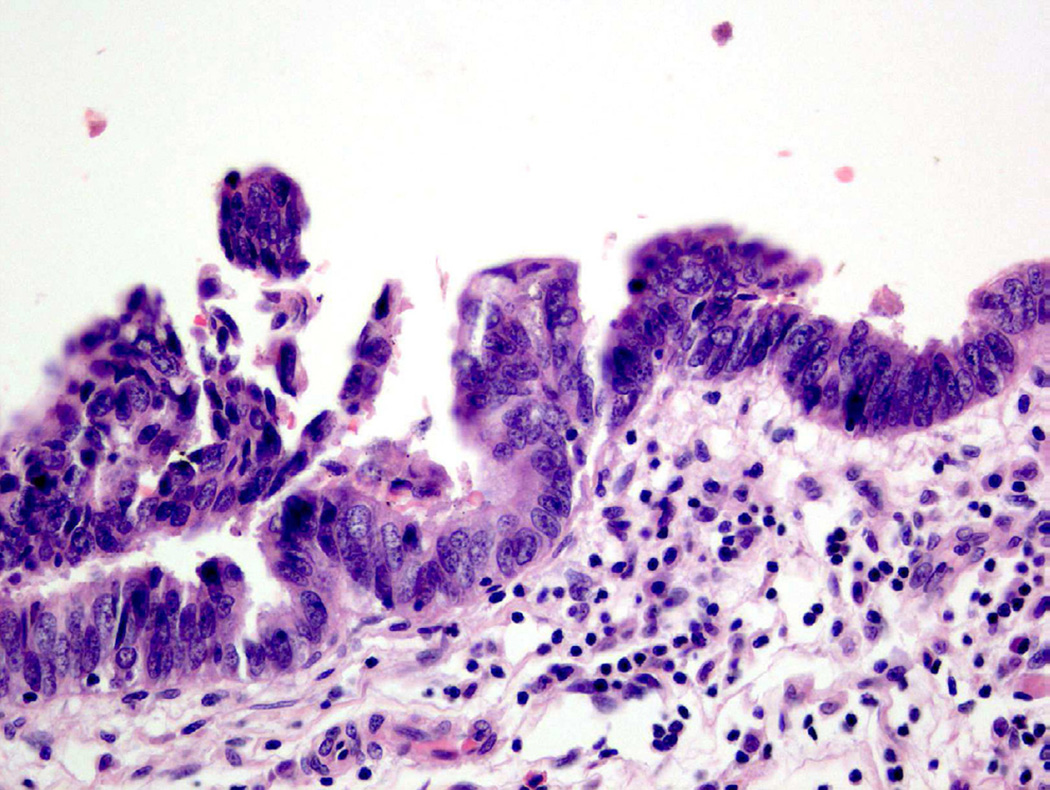

Glandular metaplasia with dysplasia

Glandular metaplasia (sometimes used interchangeably with intestinal metaplasia24) has been associated with cytologic atypia in rare cases and can be further divided into glandular metaplasia with low/high grade dysplasia27. Low-grade dysplasia shares morphologic features in common with tubular adenomas of the colon, including columnar nuclei that maintain polarity and uniformity. In contrast, adenocarcinoma in situ (glandular metaplasia with high-grade dysplasia) demonstrates overt atypia, including nuclear stratification, atypical mitoses and nuclear pleomorphism (Fig. 13)28.

Figure 13.

Adenocarcinoma in situ (glandular metaplasia with high-grade dysplasia) shows overt neoplastic alterations.